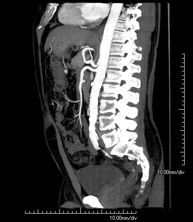

- Angio-TC aorta abdominal  Prueba diagnóstica no invasiva que consiste en el estudio de la arteria aorta abdominal obteniendo imágenes de alta definición anatómica mediante el empleo de un equipo de TC (Tomografía Computarizada) y de contraste yodado. La calidad de las imágenes permite realizar reconstrucciones en 2D y 3D gracias a estaciones de trabajo especializadas en el estudio arterial. Está indicado en aquellos pacientes con enfermedad vascular (aterosclerosis), en aneurismas de aorta, en pacientes con dolor abdominal de posible origen vascular, en estudios pre-quirúrgicos de lesiones adyacentes a la aorta abdominal como "mapa" vascular, etc. La información obtenida de forma no invasiva es indispensable para los pacientes que requieren tratamiento percutáneo o quirúrgico. En aquellos pacientes que solo requieren un seguimiento de las lesiones vasculares, esta técnica es la técnica no invasiva de elección junto con la angio-RM. Prueba diagnóstica no invasiva que consiste en el estudio de la arteria aorta abdominal obteniendo imágenes de alta definición anatómica mediante el empleo de un equipo de TC (Tomografía Computarizada) y de contraste yodado. La calidad de las imágenes permite realizar reconstrucciones en 2D y 3D gracias a estaciones de trabajo especializadas en el estudio arterial. Está indicado en aquellos pacientes con enfermedad vascular (aterosclerosis), en aneurismas de aorta, en pacientes con dolor abdominal de posible origen vascular, en estudios pre-quirúrgicos de lesiones adyacentes a la aorta abdominal como "mapa" vascular, etc. La información obtenida de forma no invasiva es indispensable para los pacientes que requieren tratamiento percutáneo o quirúrgico. En aquellos pacientes que solo requieren un seguimiento de las lesiones vasculares, esta técnica es la técnica no invasiva de elección junto con la angio-RM.

- Angio-TC aorto-ilíaco Prueba diagnóstica no invasiva que consiste en el estudio de las arterias ilíacas y la aorta abdominal obteniendo imágenes de alta definición anatómica mediante el empleo de un equipo de TC (Tomografía Computarizada) y de contraste yodado. La calidad de las imágenes permite realizar reconstrucciones en 2D y 3D gracias a estaciones de trabajo especializadas en el estudio arterial. Esta prueba está especialmente indicada como estudio pre-quirúrgico (mapa vascular) antes de intervenciones percutáneas o quirúrgicas de aorta abdominal, como el estudio complementario en pacientes con isquemia de miembros inferiores, etc. Prueba diagnóstica no invasiva que consiste en el estudio de las arterias ilíacas y la aorta abdominal obteniendo imágenes de alta definición anatómica mediante el empleo de un equipo de TC (Tomografía Computarizada) y de contraste yodado. La calidad de las imágenes permite realizar reconstrucciones en 2D y 3D gracias a estaciones de trabajo especializadas en el estudio arterial. Esta prueba está especialmente indicada como estudio pre-quirúrgico (mapa vascular) antes de intervenciones percutáneas o quirúrgicas de aorta abdominal, como el estudio complementario en pacientes con isquemia de miembros inferiores, etc.